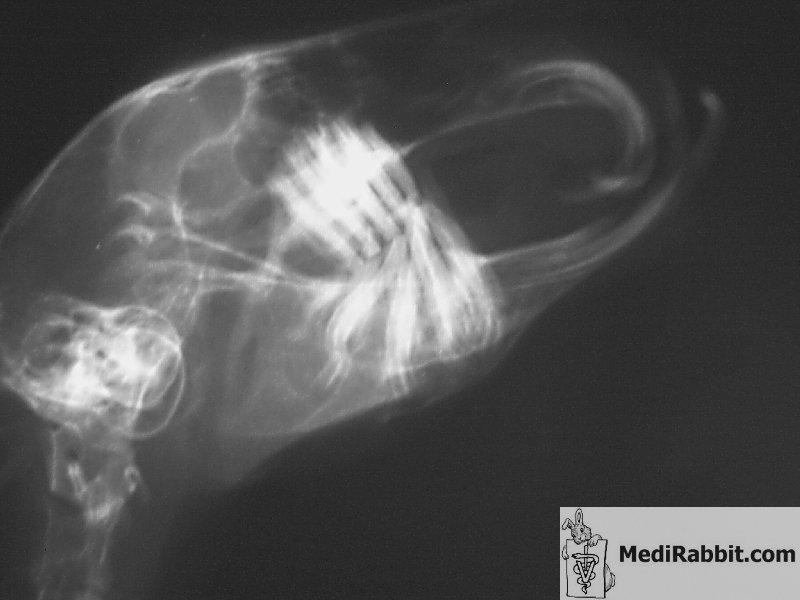

Uśpiony królik jest unieruchomiony

by zapobiec ruchom, które zakłóciłyby obraz. Najlepiej gdyby zdjęcia rentgenowskie były

zrobione z różnych katów (brzuszno-grzbietowy, boczny, skośny).

Zdjęcia muszą być nienagannej jakości, wysokiej

rozdzielczości jeśli to możliwe, by uzyskać informacje o

problemach związanymi z zębami jak np.: deformacja kości,

problemy związane z korzeniami zębów, obecność ropnia i

rozprzestrzenianie się infekcji kości żuchwy. Tomografia

komputerowa może pomóc udoskonalić diagnozę np.: lokalizując

dokładnie miejsce choroby/problemu, pokazując jego obraz,

szacując rokowanie i przewidując rezultaty leczenia.